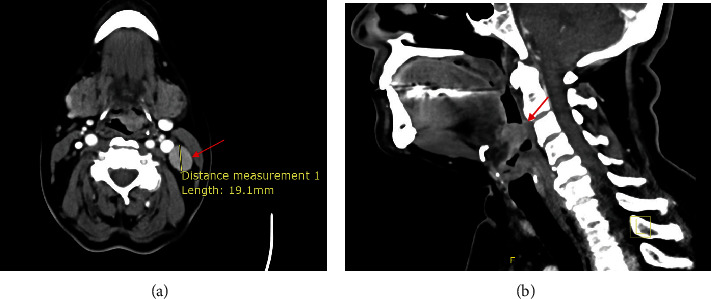

Neuroendocrine neoplasms (NENs) are rare in the head and neck region, with the larynx being the most common site. To date, nearly 700 cases of laryngeal neuroendocrine carcinoma (NEC) have been reported in the literature, with an estimated incidence as low as 0.23%. This type of cancer is more prevalent among men aged 50-83 who are heavy smokers. NENs encompass paragangliomas and epithelial neoplasms. The latter categories include neuroendocrine tumors, or typical carcinoids, and NECs, or atypical carcinoids. Due to their nonspecific and often misleading presentation, and given the rarity of this condition, optimal management lacks standardization. Treatment typically involves a combination of surgery, chemotherapy, and radiotherapy. We present a case of supraglottic laryngeal NEC in a 61-year-old female nonsmoker. The patient underwent endoscopic excision followed by adjuvant radiotherapy.